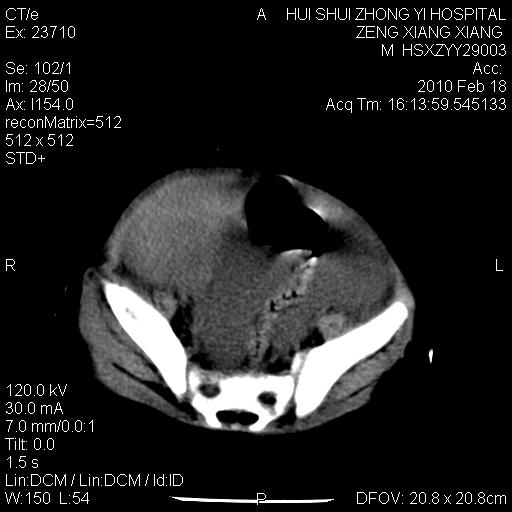

标题: PED3106:男,2岁,腹胀1月。 [打印本页]

标题: PED3106:男,2岁,腹胀1月。

定位腹膜后,肾上腺来源;

定性:恶性神经源性,肾上腺神经节母细胞瘤可能性大。

鉴别:肝母、肾母、肝脏中胚层错构瘤。

依据:年龄、有钙化,肾脏及肝脏受压移位。

肝母细胞瘤可能性大,右肾形态大体可见,不支持肾母细胞瘤,右肾移位不明显,肾上腺神经母细胞瘤可能性不大。